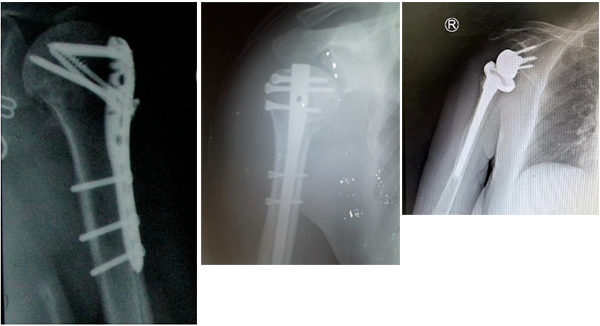

在春节假期期间,山东许多城市又迎来了一场降雪。家住临沂的张大娘因雪天路滑,不小心摔伤导致肱骨近端粉碎性骨折,慕名来到山东第一医科大学附属省立医院(山东省立医院)创伤中心就诊。创伤中心李连欣主任团队为大娘进行反式肩关节置换手术,术后恢复良好,术后左肩功能良好,李大娘及其家人对手术效果非常满意。今天,李连欣主任特别提示,瑞雪为节日增添了浓厚的喜庆氛围,给人们带来了惊喜和欢乐,但对老年人而言却增加了摔倒的风险,下雪天需警惕“雪天骨折”。

如果是一些发生在肩关节内部的骨折或者是有比较严重粉碎的骨折,在此时必须要进行手术治疗。因为此时通过保守治疗的话,往往达不到复位的要求,并且在复位之后容易移位。另外像这种严重的骨折,如果治疗不当,并发症发生率极高,远期容易出现创伤性关节炎、关节僵硬等。常用的手术方式固定包括钢板、髓内钉及关节置换。